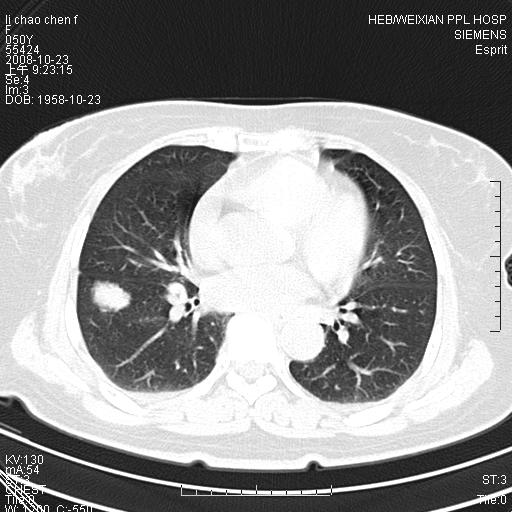

体检发现肺部肿块,现无不适。五年前曾有过哮喘病史。

先对现有的图象资料谈几点看法:病变位于右肺下叶前基底段,上部呈类圆形改变,分叶及毛刺征象不明显,下部呈不规则气腔改变,近肺门侧可见与一粗大血管相连,考虑为引流静脉影.其他肺叶相对正常所见.分析:该病灶良恶性均有可能.(现有资料来说).强化及穿刺活检有助鉴别.

考虑右肺下叶前基底段周围型肺癌可能性大。

右肺下叶前基底段占位性病变,不排除周围型肺癌可能,尽快手术为妙。

右肺下叶前基底段周围型肺癌可能性大。